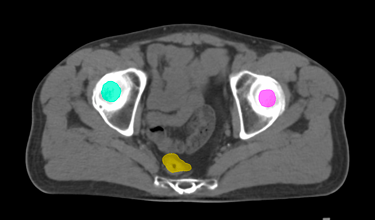

The DAM Contour features a comprehensive collection of OARs and CTVs that are ready for immediate use, without the need for manual creation of atlases or manual adjustment of data. This product includes all standard OAR and CTV structures (over 117 in total).

The Pelvis lymph node region encompasses lymph nodes that include the obturator lymph nodes, internal and external iliac lymph nodes (limited anteriorly at the level of the femoral heads), and extends up to the common iliac lymph nodes, covering the L5/S1 region.

Pelvis